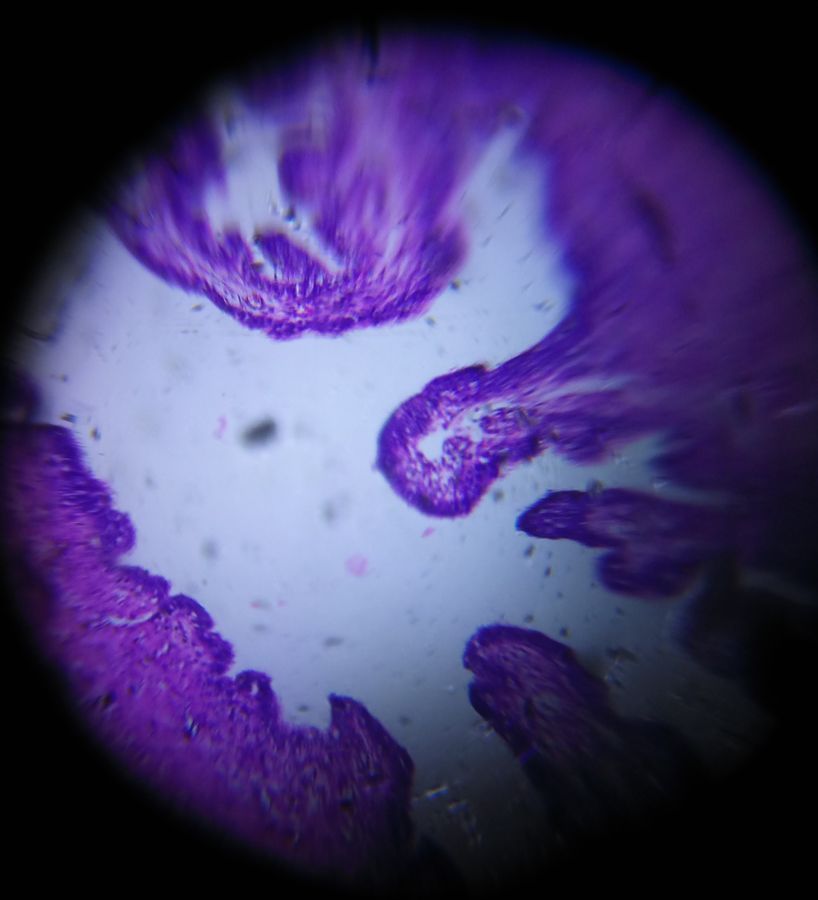

Hydrosalpinx

Applause Icon140x Magnification

Section from Fallopian tube showing Hydrosalpinx